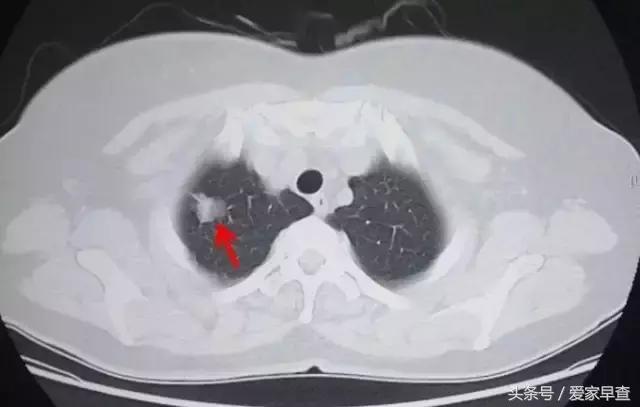

53岁女性肺部CT

这是这个人做的CT,几乎是在同一天做的CT。我们可以看到,在这个图上的一个红箭指的那个位置就是一个肺内的小结节。这个小结节为什么在胸片上看不到呢?因为在这个位置有很多的骨头都重叠到一起,这个结节密度又比较大,影子比较大,然后又比较小,所以就被挡住了。

所以这就很好理解,因为胸片是各种组织重叠到一起的,那它的清晰度是不如CT的。后来这个人发现了肺部的小结节以后,放射科大夫根据这个结节的形态、密度这些表现,就考虑是肺癌可能性很大的,后来他就做了手术。做了手术之后呢,发现是一个腺癌。

举这个例子是想说明一件事情,就是对于肺部的这个病变、包括肺的结节来说,CT的优势的是显而易见的。